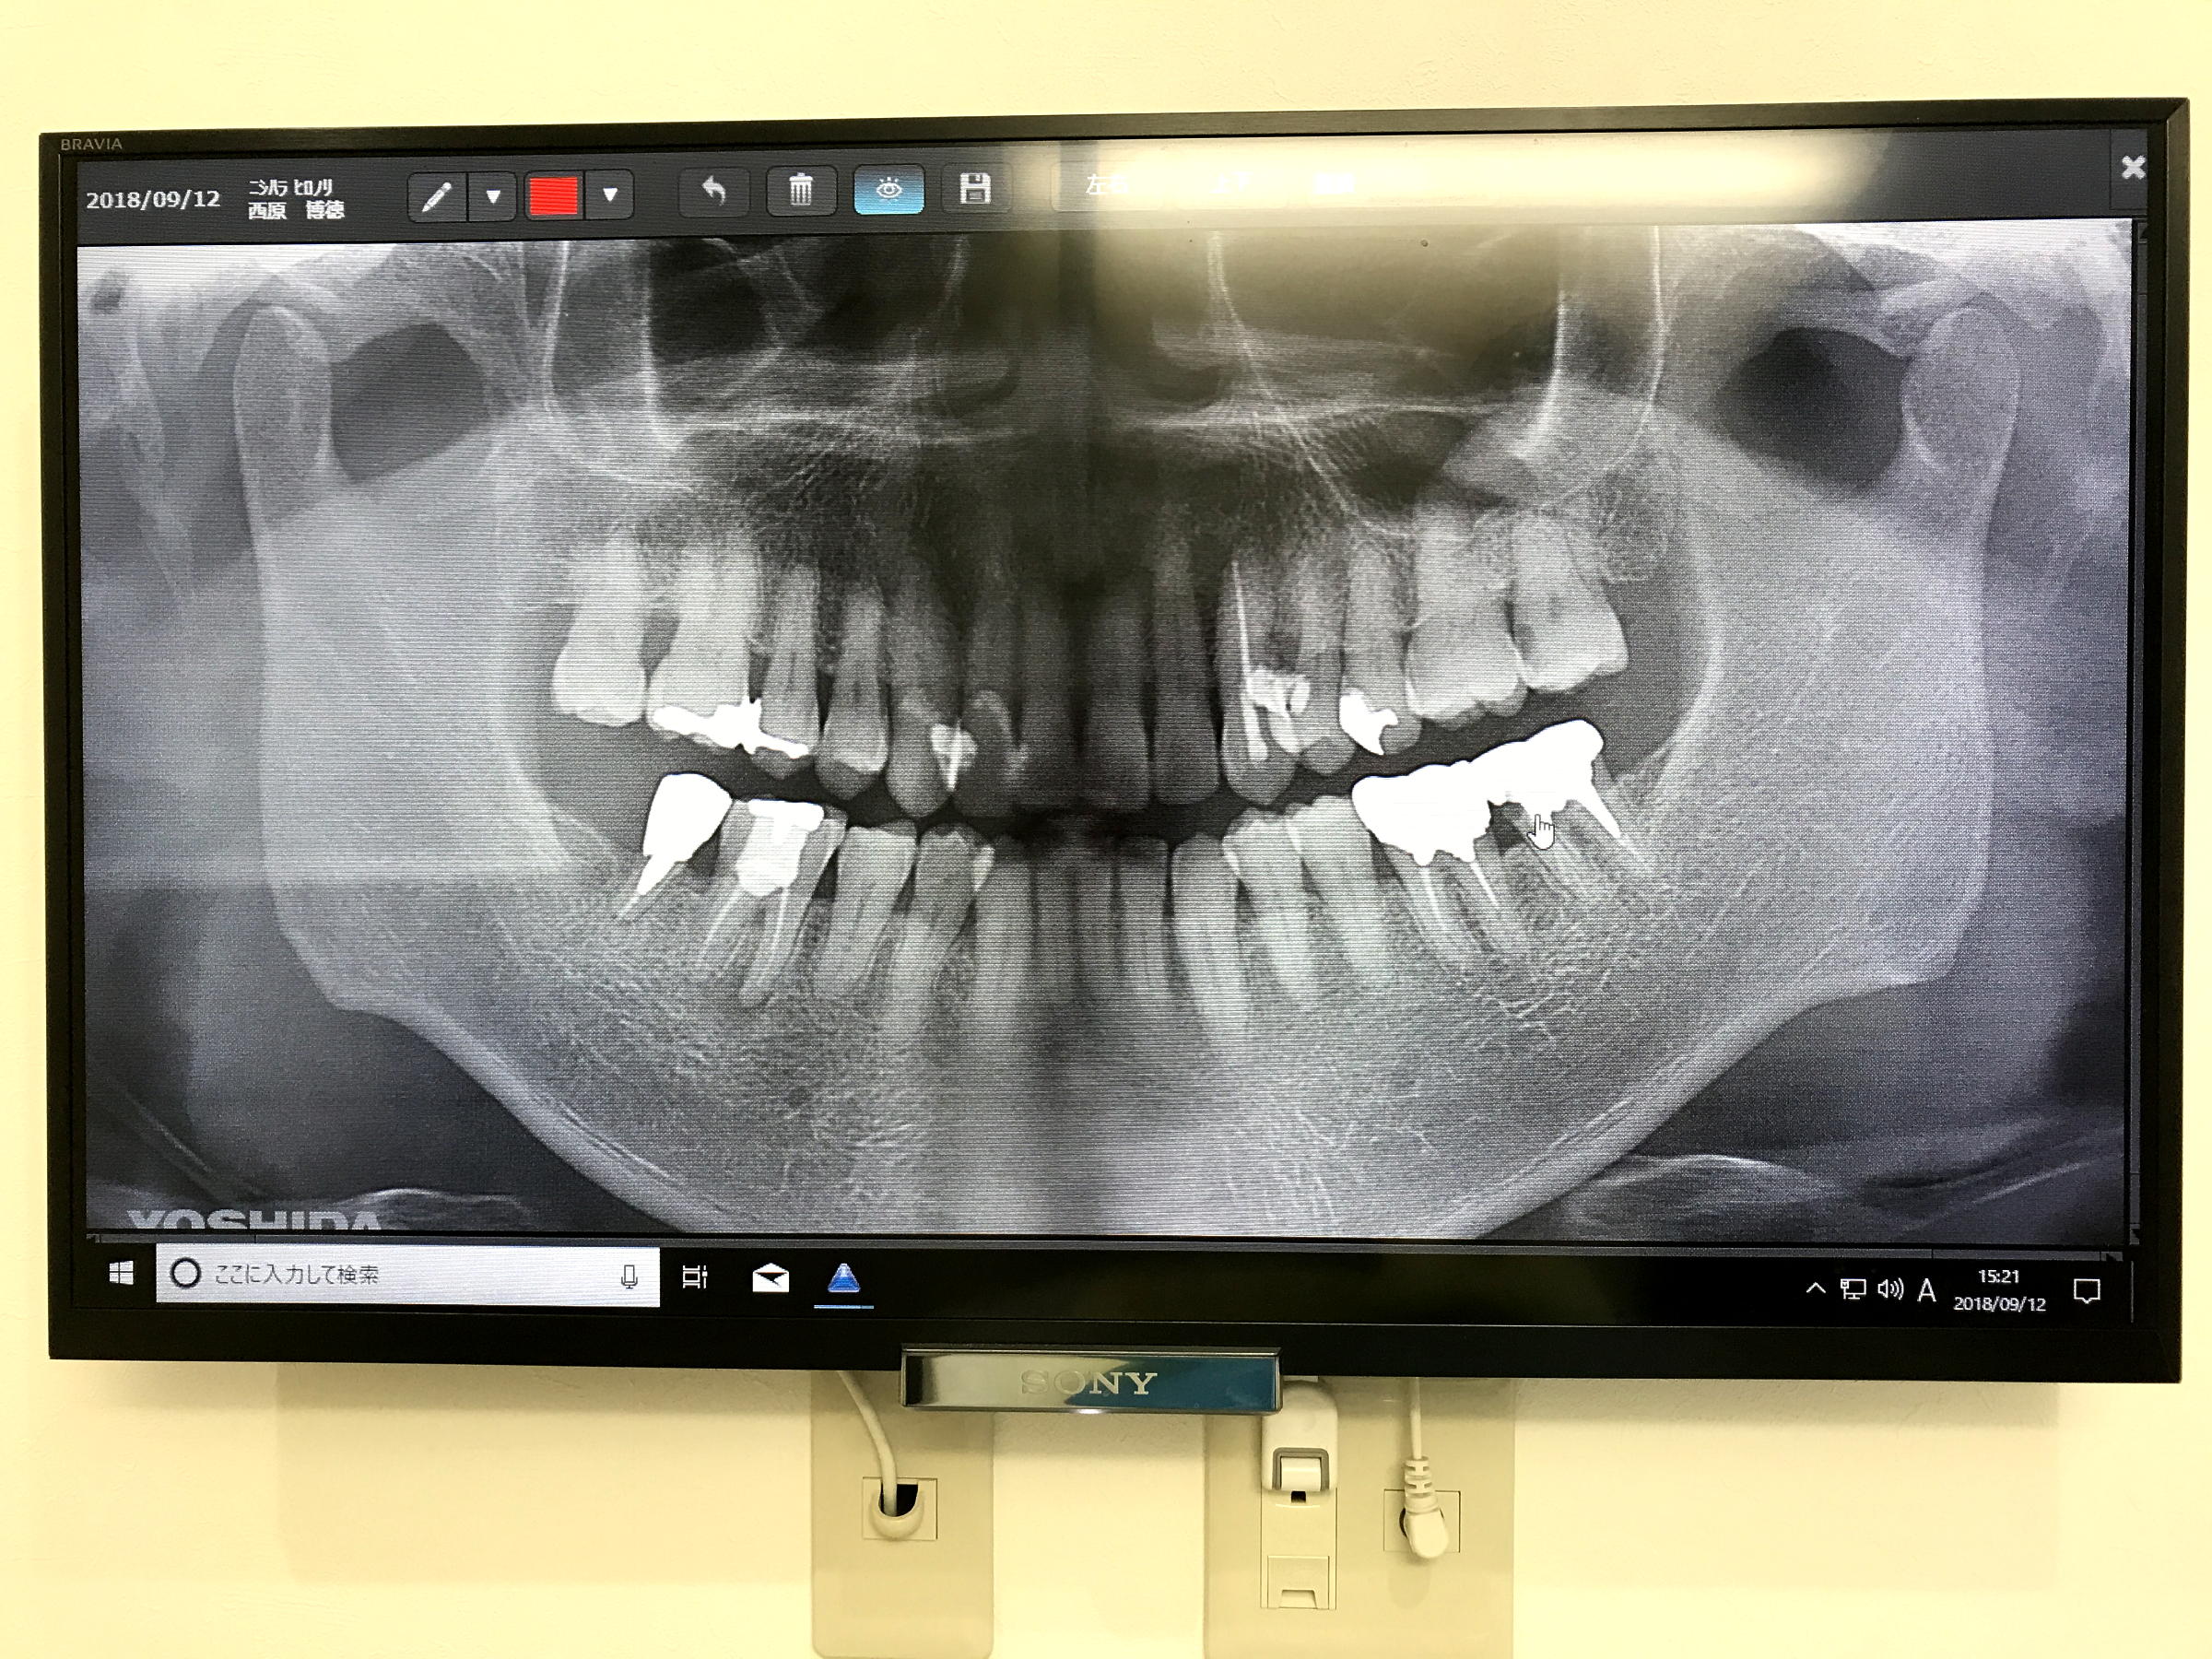

⑤ 2021.09.11 Sat.遠山歯科 診断.jpg  ④2020.10.09 Fri.遠山歯科 歯周診断.jpg  ③2018.09.12 Wed. 遠山歯科初診 歯周診断=PDF

⑤  ④  ③